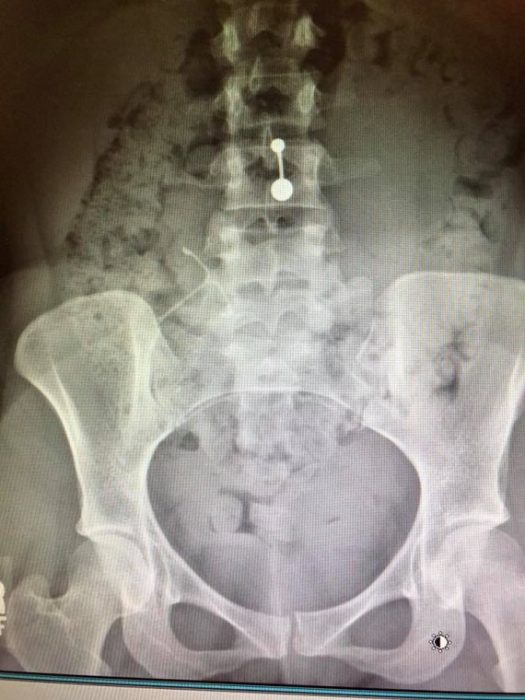

Cynthia’s IUD lodged in her uterine wall

She never wanted an IUD, but fear of becoming pregnant again so soon after having a baby led Cynthia to have an IUD implanted. She told Live Action News she immediately had horrible cramping and light bleeding, but it wasn’t until a year later that she learned something was terribly wrong.

A UTI that doctors failed to immediately diagnose led to a kidney infection and sepsis. A CT scan found the kidney infection… as well as the fact that the IUD had embedded itself in Cynthia’s uterine wall. Doctors were extremely concerned and after she had healed from the kidney infection, they scheduled surgery to remove the IUD.